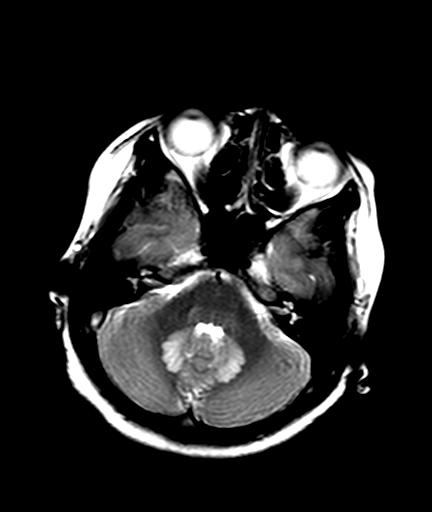

发热、头痛伴精神异常1周

脑炎,肾上腺性脑白质营养不良待除外

较对称性脑白质异常信号,深部白质t2明显低信号(铁质沉积过多?)

考虑脑白质病变,请结合临床病史及实验室检查进一步分析。

f 23岁